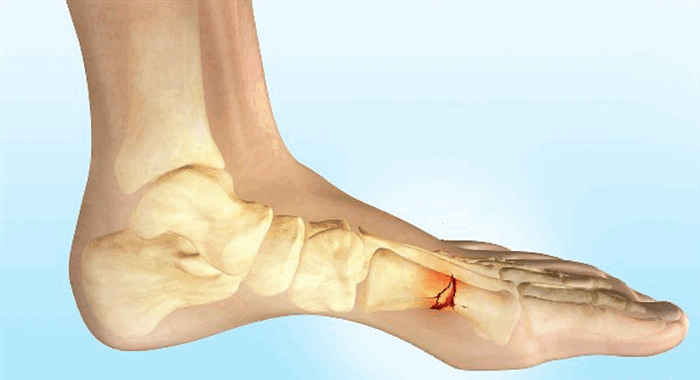

Стрессовые переломы могут охватить и пятку, и лодыжку, и среднюю часть стопы, и даже таз, крестец: в общем, все те области, которые подвергаются ударам, а мышцы вследствие усталости не могут их поглощать. Но у бегунов чаще всего страдают кости голени или стопы, ведь именно они самые рабочие для этого вида спорта. Речь идет о несущих костях – берцовой и плюсневых.

Стрессовые переломы происходят в костях, претерпевающих механическую усталость. Они являются следствием чрезмерных повторяющихся субмаксимальных нагрузок, которые создают дисбаланс между костной ресорбцией и формированием. Переломы обычно возникают в месте наибольшей нагрузки; это называют «образованием трещин». Если эту микроскопическую трещину невозможно вылечить и подвергать ее дальнейшим нагрузкам, микроповреждение увеличится, и трещина увеличивается в размерах. Такое увеличение может быть причиной перелома кости на макроскопическом уровне.

Для стрессовых переломов голени и стопы существуют оперативные и неоперативные методы лечения. Оперативному вмешательству, используемому для лечения стрессовых переломов, способствуют несколько факторов. Один из факторов – местонахождение травмы (число кровеносных сосудов в определённой части тела влияет на заживление стрессовых переломов). По некоторым данным (Brockwell и др.), таранную кость, ладьевидную кость, медиальную лодыжку, сесамовидные кости большого пальца стопы и основание пятой плюсневой кости идентифицируют как зоны высокого риска, поэтому хирургическая операция рекомендуется к проведению в первую очередь. Для плюсны возможны консервативные методы лечения, поскольку она имеет хорошее кровоснабжение. Рекомендуется полное прекращение на 4-8 недель активности, вызвавшей стрессовый перелом. Возможность переноса веса на повреждённую конечность может быть установлена по степени боли пациента при концентрировании на ней нагрузки. С другой стороны, перелом медиальной лодыжки имеет высокую степень риска из-за вероятного прогрессирования до травматического перелома. Такие переломы могут быть вылечены открытой репозицией и операцией с внутрикостной фиксацией, быстрее приводящей к реабилитации, по сравнению с методом консервативной терапии (6 — 8 месяцев).